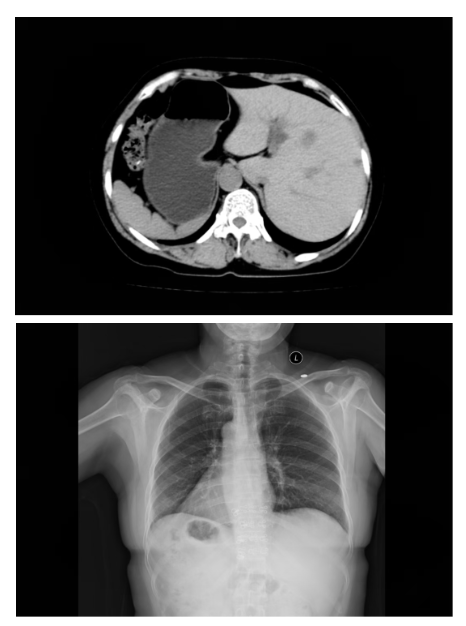

什么是“全内脏反位”?简单来说,张女士的心脏、肝脏、胆囊、脾胃等所有胸腹腔器官,位置都与正常人完全左右对调。就像照镜子时看到的自己,医学上形象地称之为“镜面人”。

这种先天变异的发生率极低,大约每万人中仅有1例。对于普通人来说,这只是一个有趣的医学名词;但对于即将接受手术的张女士和她的主刀医生来说,这意味着巨大的挑战。